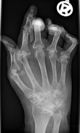

أشعة اكس على يد مصابة بالروماتويد

ويتم التأكد من التشخيص بعمل فحص للدم والذي يشير هنا إلى ارتفاع في نسبة ترسب الدم ESR ووجود عامل الروماتويد RF وكذلك وجود سي ـ ر ـ بروتين CRP وكذلك عمل أشعة سينية وهي توضح هنا تغيرات في المفاصل مثل تآكل المفاصل وتشوهها وهشاشة العظام.